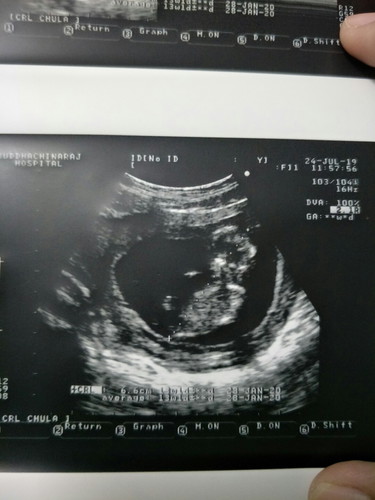

อยากถามแม่ๆหน่อยค่ะว่าเราจะเชื่ออายุครรภ์ตามในใบซาวหรือสมุดชมพูค่ะ ในสมุด 12w+5

สมุดชมพูคำนวณตามปจด.ครั้งสุดท้ายของแม่ ใบซาวดูจากความยาว น้ำหนักน้องค่ะ

ถือว่าใกล้เคียงกันนะคะ ปกติของเราอิงตามอายุครรภ์จริงค่ะ